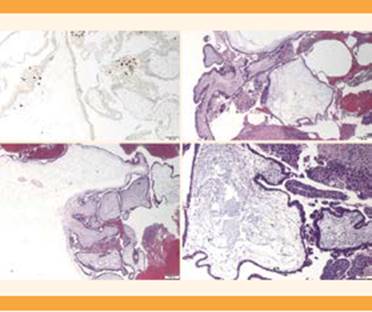

El diagnóstico histológico fue de mola hidatiforme completa, en el que se especificó que, ante la sospecha clínica de mola invasiva, se precisaba mayor muestra de legrado endometrial o, bien, pieza de histerectomía para demostrar la existencia de vellosidades coriales en el espesor del miometrio. En la descripción microscópica de la pieza destacaba la existencia de abundantes vellosidades coriales hidrópicas asociadas con una importante proliferación trofoblástica, sin identificar estructuras embrionarias y expresando el marcador p57 (Figura 3).

Figura 3 Descripción microscópica de la muestra. Abundantes vellosidades coriales hidrópicas asociadas con importante proliferación trofoblástica. Alrededor se observa una proliferación del trofoblasto con células moderadamente atípicas, sin identificar estructuras embrionarias. En el estudio inmunohistoquímico de p57 se demuestra la pérdida de expresión en células estromales y del citotrofoblasto, con expresión en el sincitiotrofoblasto y trofoblasto intermedio.